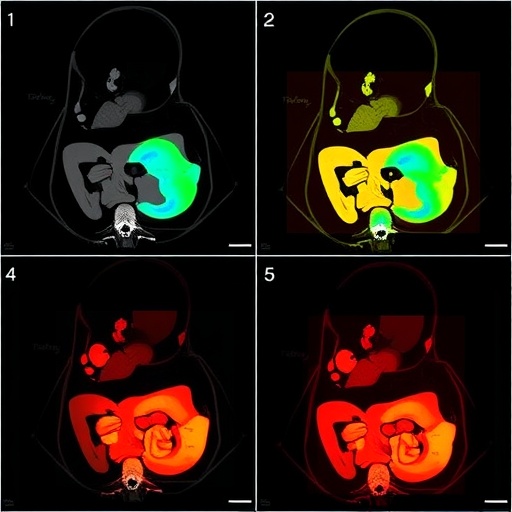

The study meticulously reviews the imaging modalities utilized to diagnose and monitor MMIHS across different stages of patient development, particularly before, during, and after the neonatal period. It highlights the importance of early detection and the nuances involved in interpreting various imaging studies. Radiologists and clinicians alike will find value in the visual representation of MMIHS through the lens of advanced imaging techniques.

To complement these imaging techniques, computed tomography (CT) is also explored within the study. Although CT scans expose patients to radiation, its capacity to provide exceptional cross-sectional images can be invaluable in specific clinical scenarios. The study raises awareness about the judicious use of CT, aiming to balance the need for accurate diagnosis against the potential risks involved, particularly when managing a vulnerable pediatric population.

The imaging findings presented in the study are not merely academic; they reflect real patient cases with diverse presentations of MMIHS. These cases emphasize the variability in features and the challenges faced during diagnosis. The pictorial review serves as a visual educational tool for healthcare professionals, promoting awareness and understanding of this syndrome.